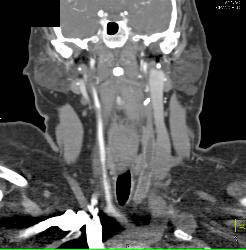

Jugular Vein Thrombosis